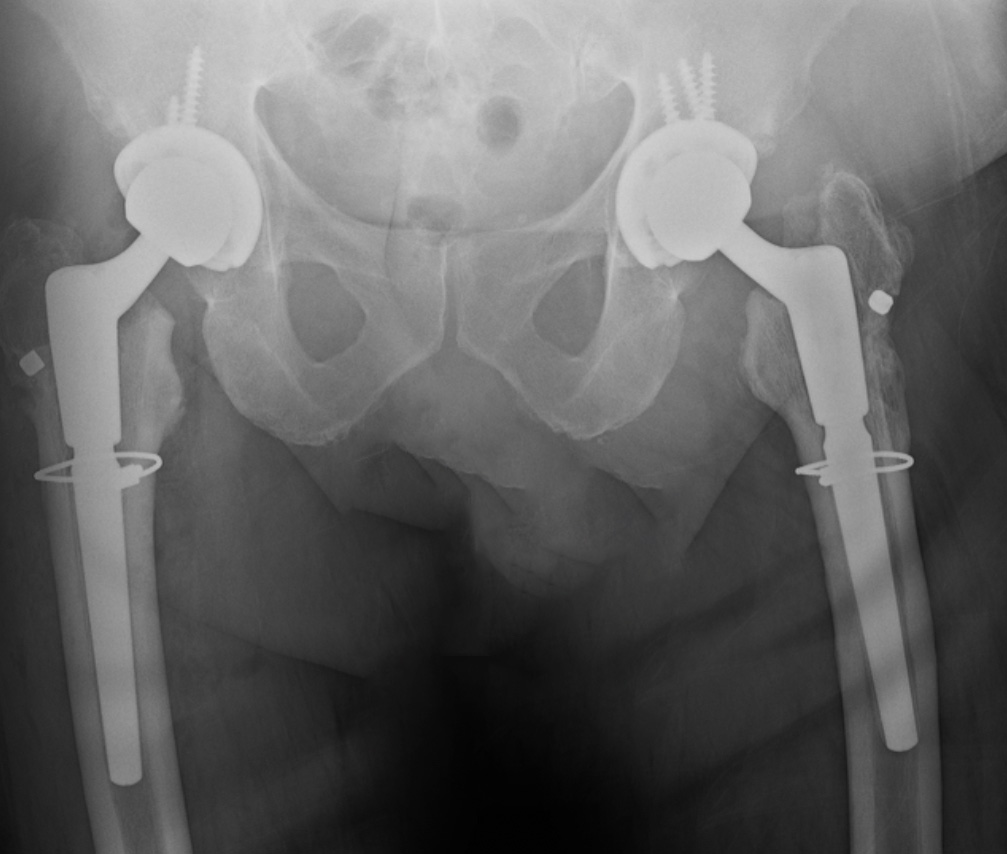

Hip Replacement